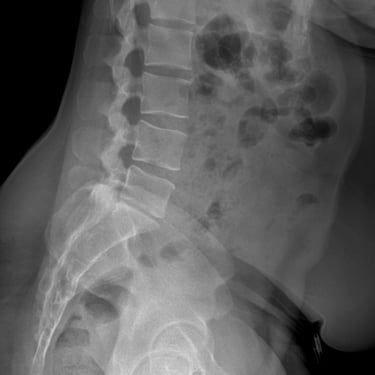

Manejo quirúrgico de la hernia lumbar con inestabilidad: enfoque moderno con FTP y TLIF

La hernia lumbar con inestabilidad vertebral es una patología frecuente que causa dolor lumbar persistente, ciática y limitación funcional, afectando la calidad de vida del paciente. Cuando el tratamiento conservador no logra resultados adecuados, la cirugía se convierte en la mejor opción terapéutica. La fijación transpedicular con tornillos (FTP) junto con la técnica TLIF (Transforaminal Lumbar Interbody Fusion) permite estabilizar la columna, descomprimir las estructuras nerviosas y lograr una adecuada fusión ósea. Este abordaje, especialmente mediante técnicas mínimamente invasivas (MISS), ofrece múltiples beneficios, como menor daño muscular, menor dolor postoperatorio y recuperación más rápida, facilitando el retorno temprano a las actividades cotidianas con mejores resultados clínicos.